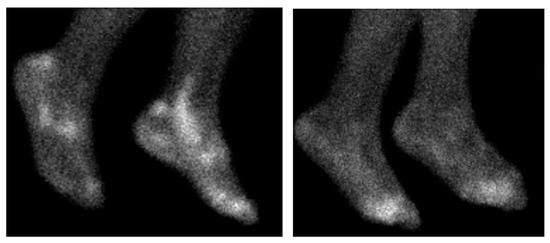

Despite important advancements in arthritis research, significant challenges remain, particularly in the early diagnosis of these conditions and the development of personalized treatments tailored to individual patients. This Special Issue aims to address these issues by focusing on innovative diagnostic methods, such as advanced imaging techniques, and a deeper understanding of disease mechanisms. It will also explore cutting-edge treatments, including disease-modifying anti-rheumatic drugs (DMARDs), biologics, and targeted therapies.

A key goal of this Special Issue is to improve how healthcare professionals differentiate between similar types of arthritis, enabling quicker and more accurate diagnoses, and to better assess the extra-articular manifestations of these diseases.